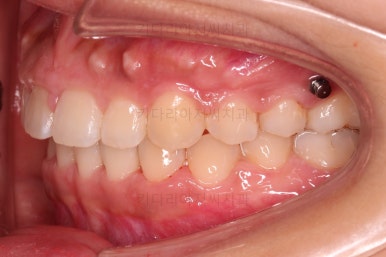

옆라인에서 입은 튀어나온 느낌은 없지만 턱끝만 살짝 볼륨감이 있는 편이었어요.

그렇다고 주걱턱은 아닙니다.

과개교합은 거의 개선이 되었고요.

위아래 치열의 중앙이 서서히 맞아지는 느낌이 드시나요?

조금만 더 하면 되겠네요.

중앙선을 맞추고 교합도 잘 맞추고 마무리를 합니다.